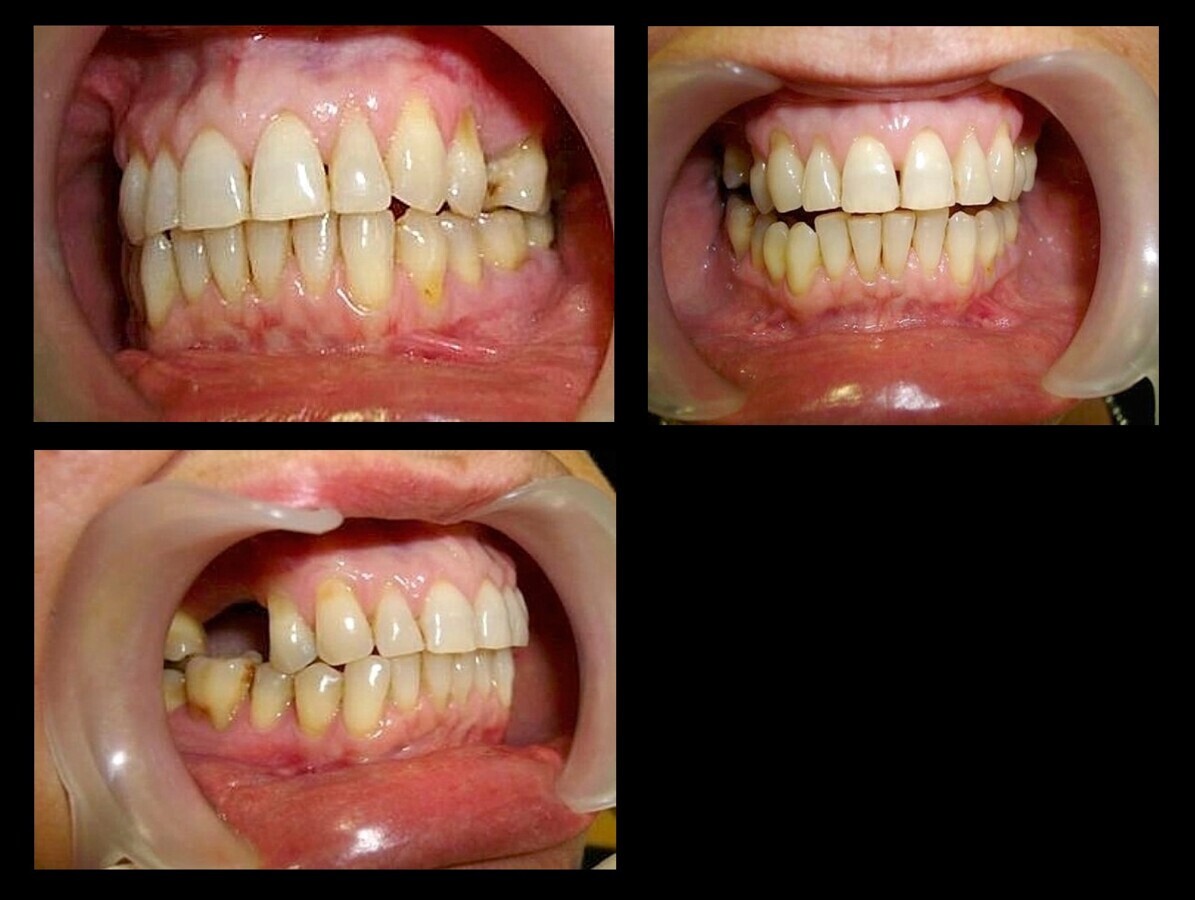

El tratamiento dental de los pacientes que sufren de cáncer depende del estado de su salud oral, que puede ser deficiente, como en el caso del paciente bajo tratamiento con tamoxifeno (1), en estado de salud oral aceptable, como en el paciente siendo tratado con el mismo medicamento (2) o en buen estado de salud oral, en el caso de un paciente con cáncer de colón (3).

2. b) Mal estado bucal (higiene pobre, enfermedad periodontal grave, y más de 20 caries) (Figura 1).

Figura 1. Paciente de 60 años, en mal estado de salud oral, y en tratamiento con tamoxifeno. En estos pacientes puede ser aconsejable realizar una edentación total.

1. c) Estado bucal regular (no enfermedad periodontal grave, menos de 20 caries e higiene regular) (Figura 2).

Figura 2. Paciente de 66 años de edad, en estado de salud oral aceptable, y en tratamiento con tamoxifeno. Se debe concienciar al paciente sobre higiene oral, hacer aplicación de flúor y tratamiento conservador de aquellos dientes que puedan ser restaurables.

1. d) Estado bucal bueno (Figura 3) (no enfermedad periodontal, caries casi ausentes y buena higiene).

Figura 3. Paciente de 65 años de edad, en buen estado de salud oral, con antecedentes de cáncer de colón tratado a los 61 años. Se debe concienciar al paciente sobre higiene oral, hacer aplicación de flúor y tratamiento conservador de aquellos dientes que puedan ser restaurables, cirugía preprotésica y periodontal, eliminar prótesis metálicas si se va a recibir radioterapia.